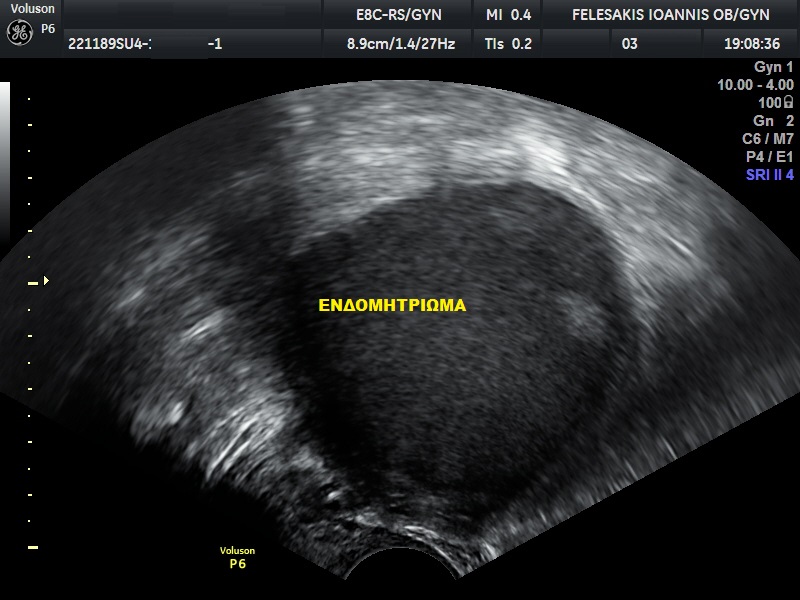

Πώς γίνεται η διάγνωση της νόσου; Την υποψία μας για την ύπαρξη ενδομητρίωσης, μπορούμε να την αντλήσουμε από τη λήψη ενός καλού ιστορικού, τη γυναικολογική εξέταση, τον υπερηχογραφικό έλεγχο των έσω γεννητικών οργάνων της γυναικας και τέλος τη χρήση της μαγνητικής τομογραφίας. Η διενέργεια αιματολογικών εξετάσεων δεν αποδεικνύει την ύπαρξη ενδομητρίωσης. Ο μοναδικός τρόπος για να τεθεί η διάγνωση της πάθησης είναι η διενέργεια λαπαροσκόπησης και η λήψη βιοψιών από τις ύποπτες περιοχές. Η ταξινόμηση της νόσου (στάδιο Ι-ΙV) γίνεται με κριτήριο το μέγεθος των εστιών, την παρουσία και την έκταση των συμφύσεων καθώς επίσης και την επέκταση της νόσου (στις ωοθήκες και σε άλλα όργανα). Η εικόνα της ενδομητρίωσης ποικίλει και, δυστυχώς, δεν έχει βρεθεί τρόπος να συσχετίσουμε τα συμπτώματα της ασθενούς με τον βαθμό ενδομητρίωσης (Ι-ΙV).

Πρέπει να οδηγούμαστε σε χειρουργική επέμβαση κάθε φορά που εμφανίζεται μια ενδομητριωσική κύστη; Υπάρχουν συγκεκριμένα κριτήρια βάσει των οποίων χειρουργούμε μία ενδομητριωσική κύστη και τα οποία ο Γυναικολόγος-Χειρουργός πρέπει να υπολογίσει. Σε πολλές περιπτώσεις άλλωστε, είναι πιο ωφέλιμο για τη γυναίκα να μη χειρουργηθεί.

Ενδομήτριο: Το εσωτερικό στρώμα της μήτρας, αυτό που καλύπτει την εσωτερική της κοιλότητα. Ενδομητρίωμα: Κύστη στην ωοθήκη γεμάτη με αίμα που δημιουργείται όταν η ενδομητρίωση προσβάλλει τις ωοθήκες. Σοκολατοειδής κύστη: Κύστη στην ωοθήκη γεμάτη με αίμα που δημιουργείται όταν η ενδομητρίωση προσβάλλει τις ωοθήκες. Λέγεται σοκολατοειδής γιατί το αίμα που περιέχεται στην κύστη σταδιακά παίρνει καφέ σκούρο χρώμα. Στειρότητα:η απόλυτη βιολογική αδυναμία τεκνοποίησης Υπογονιμότητα: η ακούσια αδυναμία ενός ζευγαριού να επιτύχει σύλληψη και να ολοκληρώσει κύηση μετά από τουλάχιστον ένα έτος τακτικών σεξουαλικών επαφών χωρίς αντισύλληψη.